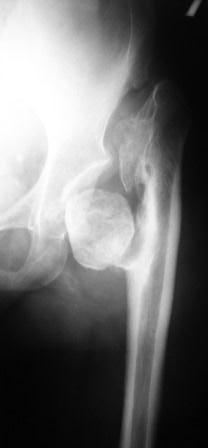

Хотелось бы услышать Ваше мнение по лечению больной 45 лет. Никаких медицинских документов нет. Со слов больной лечили по поводу врожденного вывиха бедра.

В 1985г. остеотомия нижней трети бедра и

удлинение в аппарате Илизаровна 5см. В настоящее время укорочения конечности нет. Обратилась по поводу выраженного болевого синдрома, который усилился в течение последних двух лет. Судя по рентгенограммам - имел место coxa vara coli lisis с патологическим вывихом бедра.

Любое низведение бедра даст грубое удлинение конечности. остеотомии в условиях головки-секвестра мне кажутся бесперспективными.